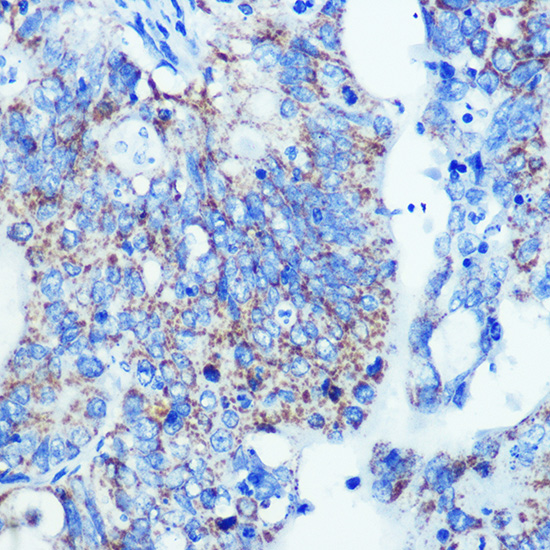

Applications: |

WB,IHC,IF |

appl_detail: |

WB 1:500 - 1:2000 |